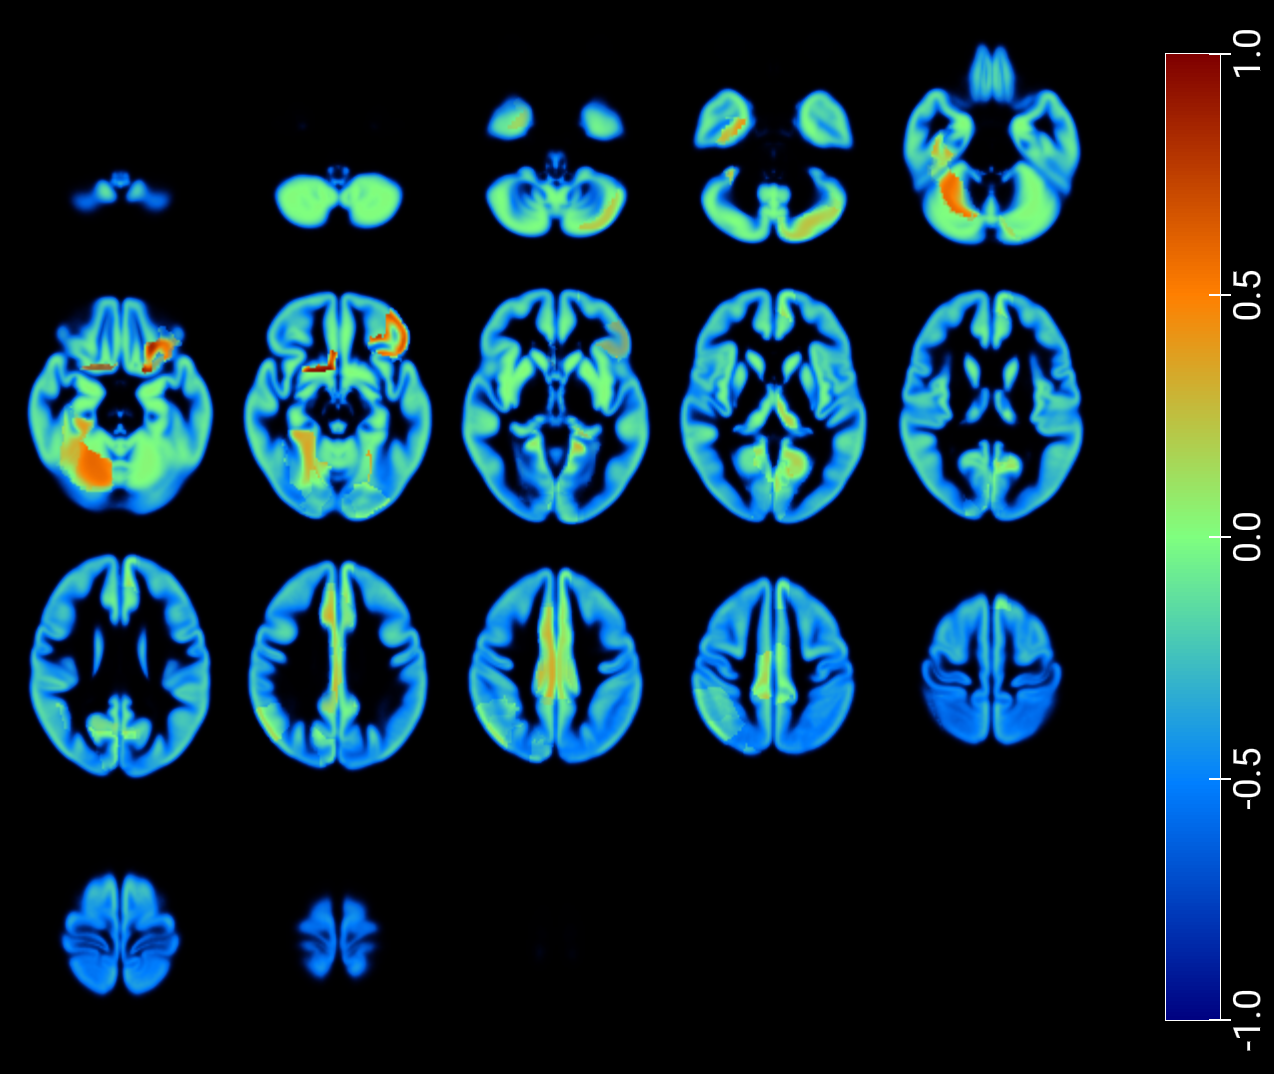

As a critical baseline, we report classification results based on latent features in [2] and provide visualizations of the maximum Pearson correlation values between latent-space activations -projected onto low-dimensional spaces- and region-wise average intensities, stratified by class, and fused with GM MRI (figures 7 and 8). These results explore the correspondence between network activations and anatomical signal distributions and whether it differs across clinical conditions (e.g., AD vs. NOR). This offers a transparent alternative to assess model interpretability and underscores the need for more rigorous and nuanced validation practices in the field.

An inspection of the groups and regions with the highest correlations reveals overlapping areas across clinically relevant comparisons in image reconstruction, as summarized for the t-SNE–based projections in Table 2. These regions correspond closely to those identified through the SHAP analysis presented in the following section (Table 3).

Finally, we applied the Latent–Regional Correlation Profiling (LRCP) framework to generate spatial maps that highlight how latent components relate to regional brain variation across different diagnostic comparisons. Specifically, we focused on the three binary groups and, for each case, projected the regional accuracy of the latent–region associations onto an anatomical atlas. By computing corrected significance rates for each latent–region pair and averaging them across subjects, we obtained accuracy maps that indicate which brain regions consistently encode discriminative information for each comparison. These maps provide an interpretable visualization of the spatial distribution of diagnostic relevance, facilitating a region-wise comparison of how latent dimensions capture biologically meaningful variation across the different binary groups.